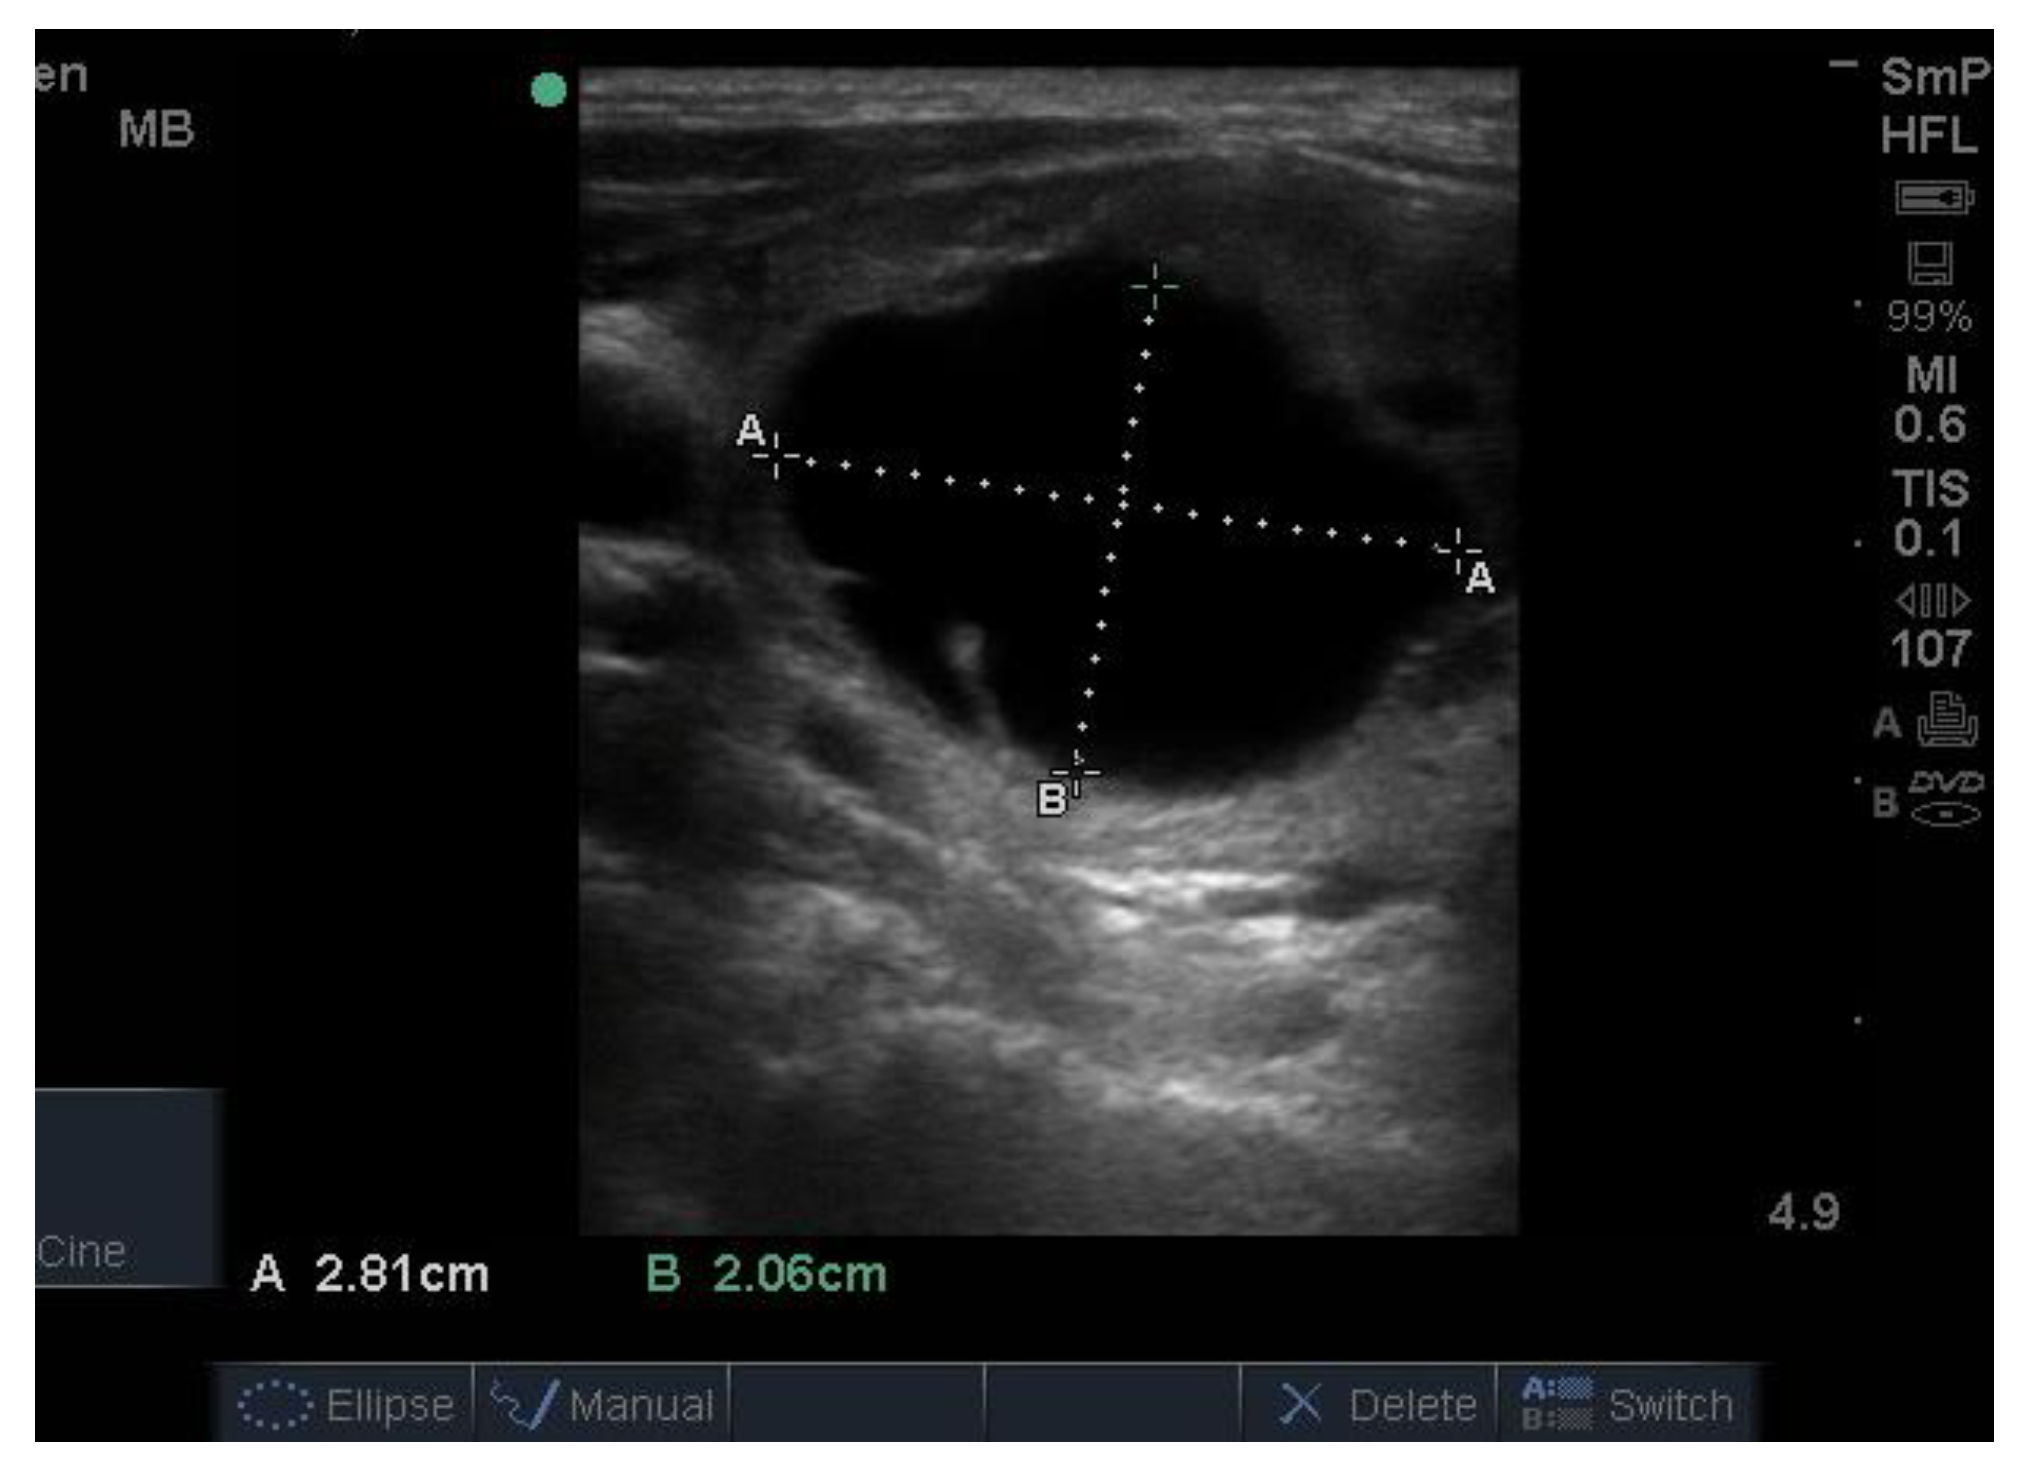

14. Parathyroid Disease

Because the senior author (JW) routinely measures serum calcium, parathyroid hormone (PTH) and vitamin D in his patients, hyperparathyroidism due to a benign adenoma of one of the parathyroid glands appears to be much more common than previously thought. The parathyroid glands are hidden behind the thyroid and so may be obscured by thyroid nodules, although they can often be seen in the longitudinal view below the lobes, as a hypoechoic lesion of around 1 cm in diameter (Figure 18).

The parathyroid adenoma is typically hypoechoic by comparison to the nearby thyroid tissue, which is consistent with the author’s experience. However, only about 50% of subsequently proven parathyroid adenomas are seen on ultrasound and even the Sestamibi nuclear scan fails to pick them up in about 30% of cases.

Figure 18. Thyroid ultrasound from a patient with hyperparathyroidism showing a hypoechoic lesion below the right thyroid lobe that was confirmed to be a parathyroid adenoma at surgery.